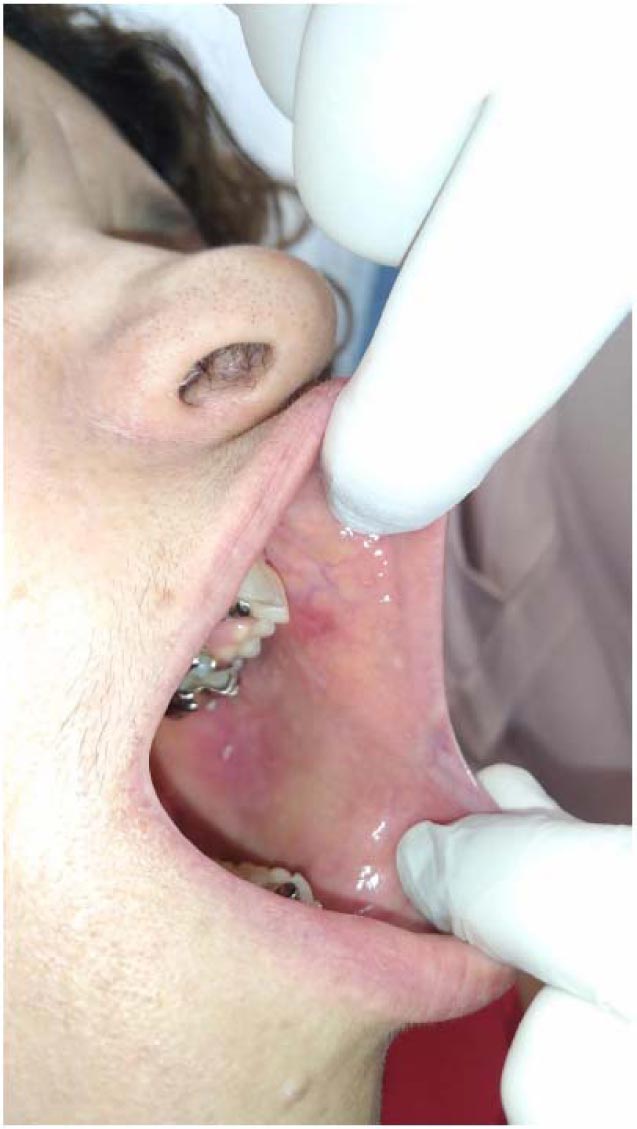

A high-intensity diode laser with a wavelength of 980 nm (Thera Lase Surgery DMC, São Carlos, Brazil) was used in a contact-mode technique under local anesthesia. Irradiation was delivered using a handpiece connected to a single-use fiber (300 μm in diameter) that was set for use in continuous-wave mode, at a power output of 1.5, for excising the lesion. The diode laser provided an optimum combination of clean cutting of the tissue and hemostasis (Fig. 2). The excised tissue was sent for histopathological study to confirm the clinical diagnosis (Fig. 3).

The patient was provided with post-treatment instructions. After a one-week follow-up the wound healed without complications and no signs of infection, and it was not necessary to use the analgesic medication after surgery (Figs. 4 and 5).